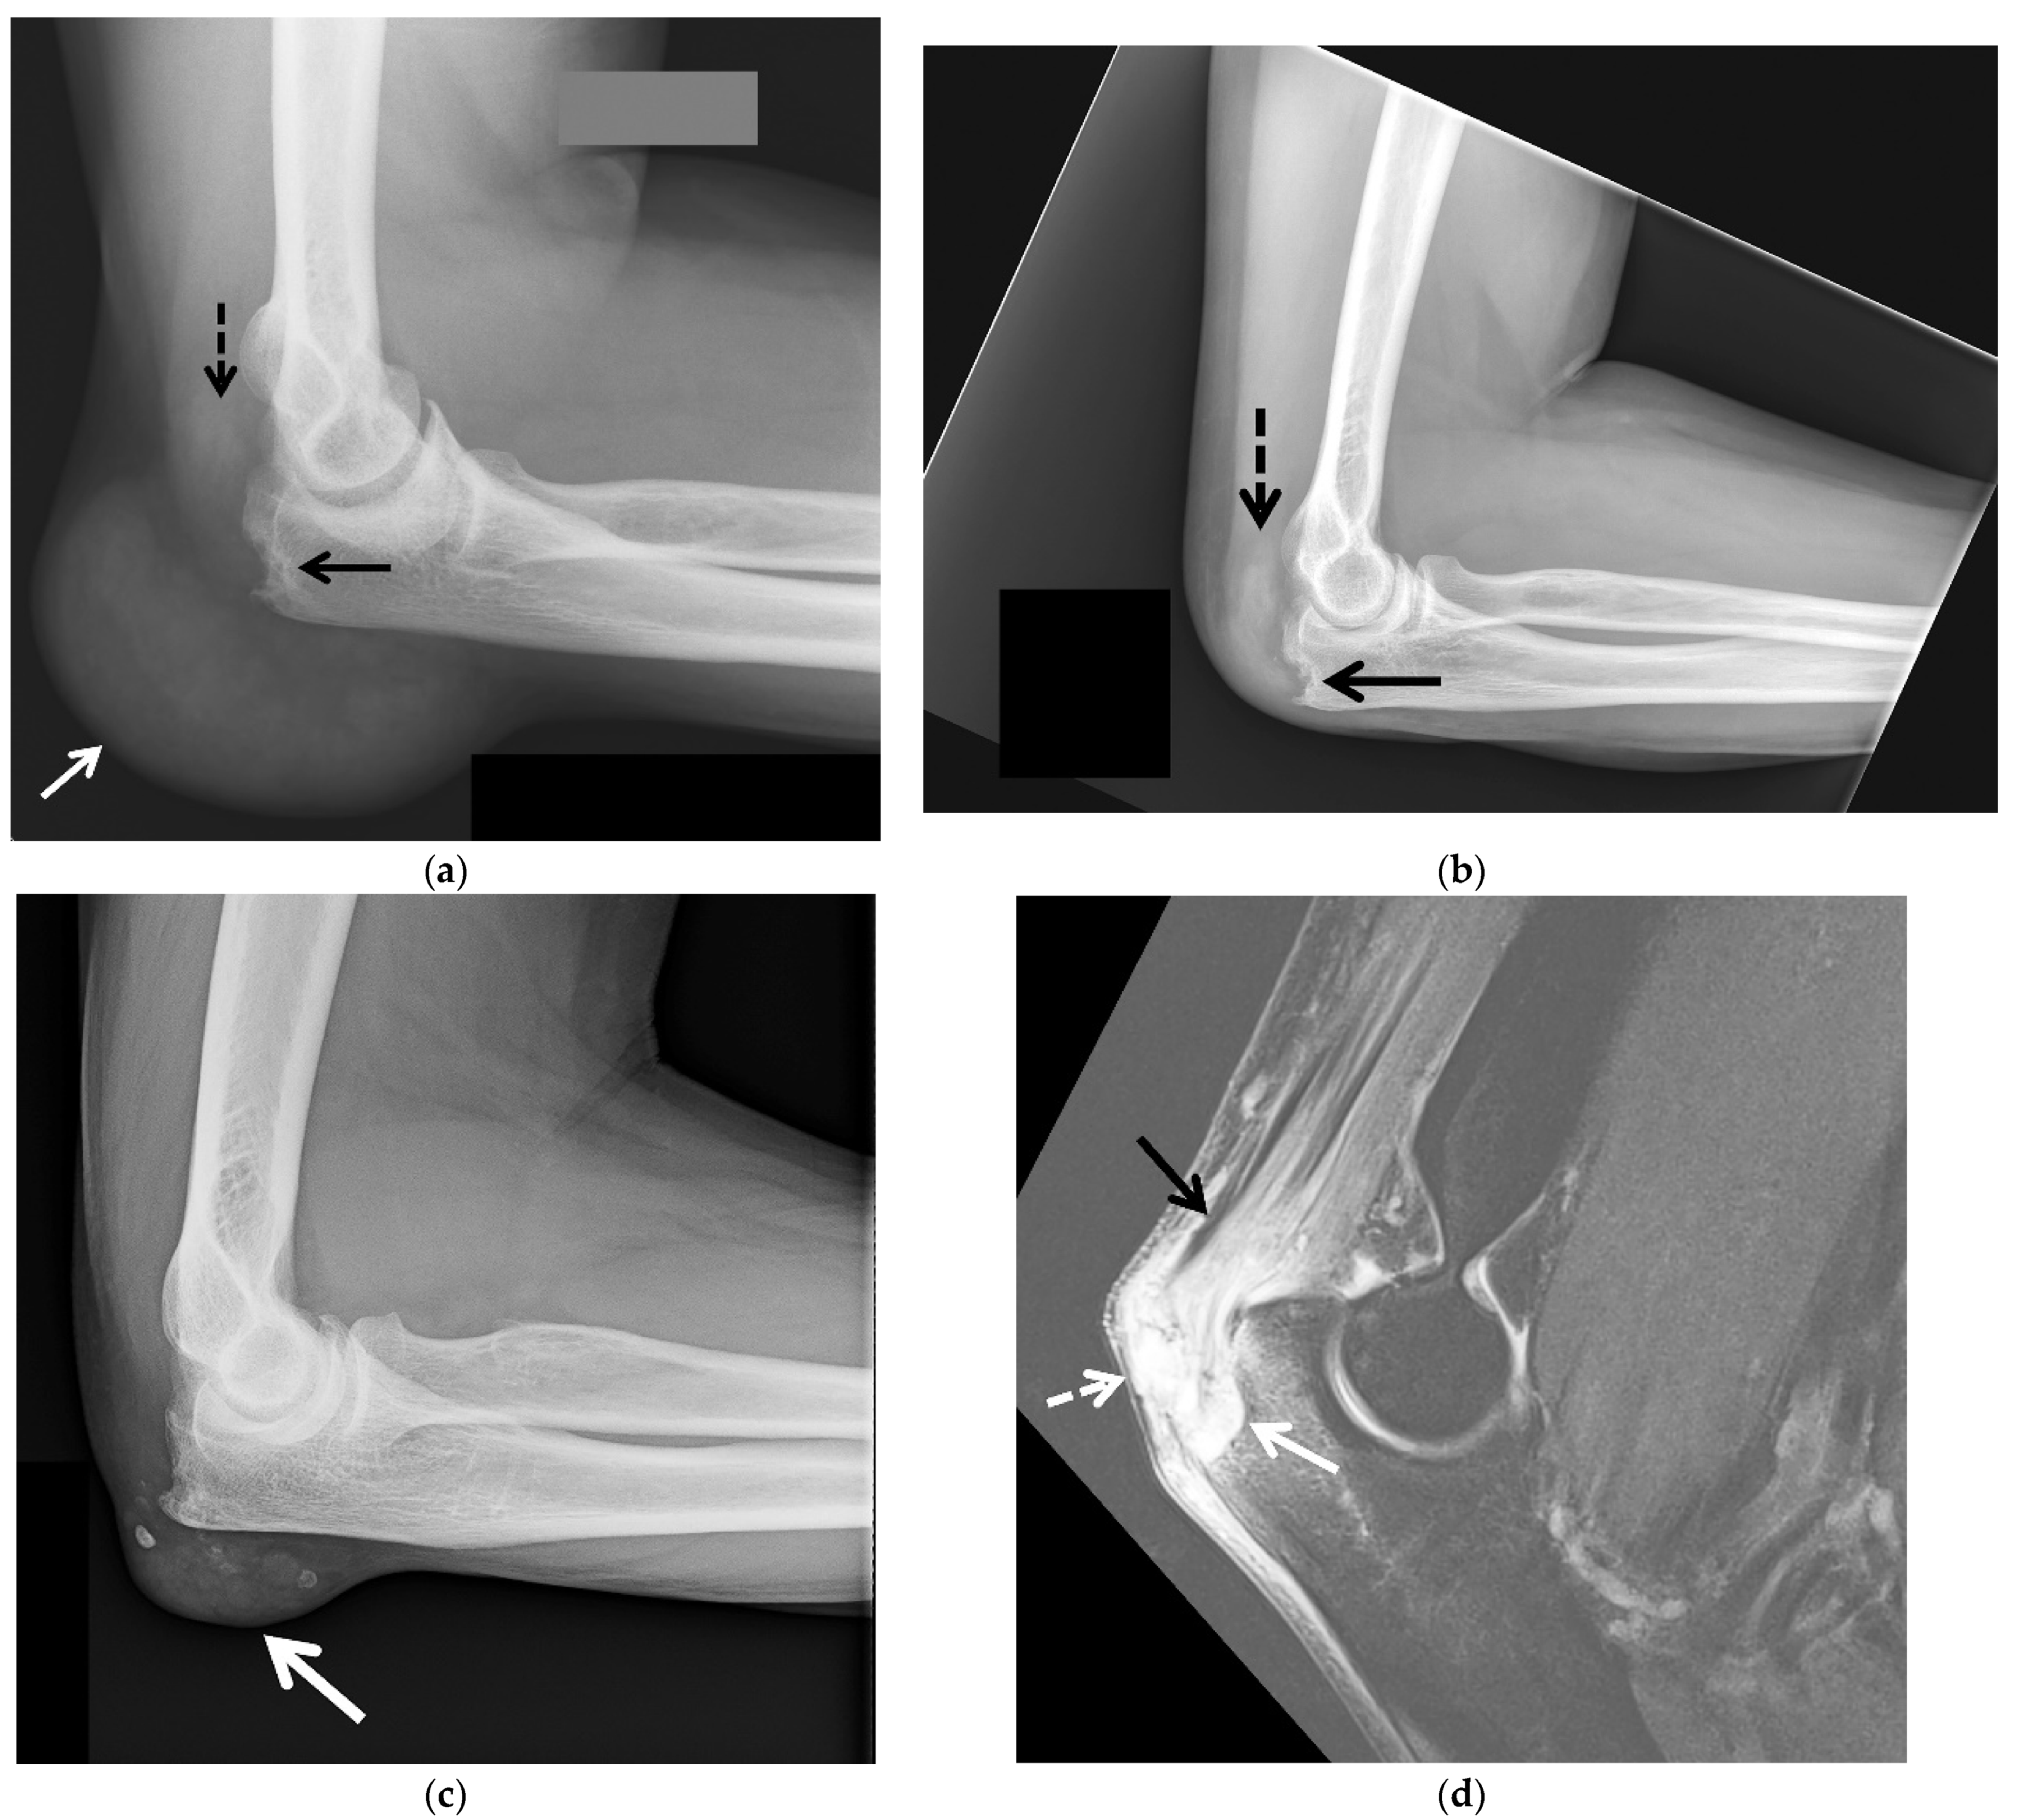

3.1. Radiographs